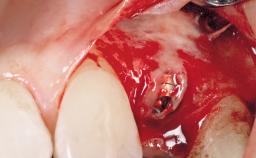

Immediate Flapless Placement of an Implant in a Maxillary Left Central Incisor Site

A 29-year-old female patient presented for treatment to replace the upper left central incisor tooth with an implant- supported restoration. The tooth had been intermittently symptomatic for the previous 12 months. The tooth had originally suffered trauma about 15 years previously. Several endodontic treatments had been performed, including an apicectomy procedure to retain the tooth. The patient was healthy and a non-smoker. She had reasonable expectations in regard to esthetic outcomes and the risk of marginal tissue recession following treatment. At medium smile, the gingival margins of the upper teeth were visible, with a display of 3 to 4 mm of the gingival margins. Gingival recession of tooth 21 and a discrepancy in the gingival levels between teeth 11 and 21 was observable during normal speech and smile.

Placement Protocol Immediate implant placement

Tooth Site Maxillary incisor or canine

Socket Morphology Single-root socket

Socket Integrity Damage to one or more bone walls

Bone Volume Damage to one or more socket walls